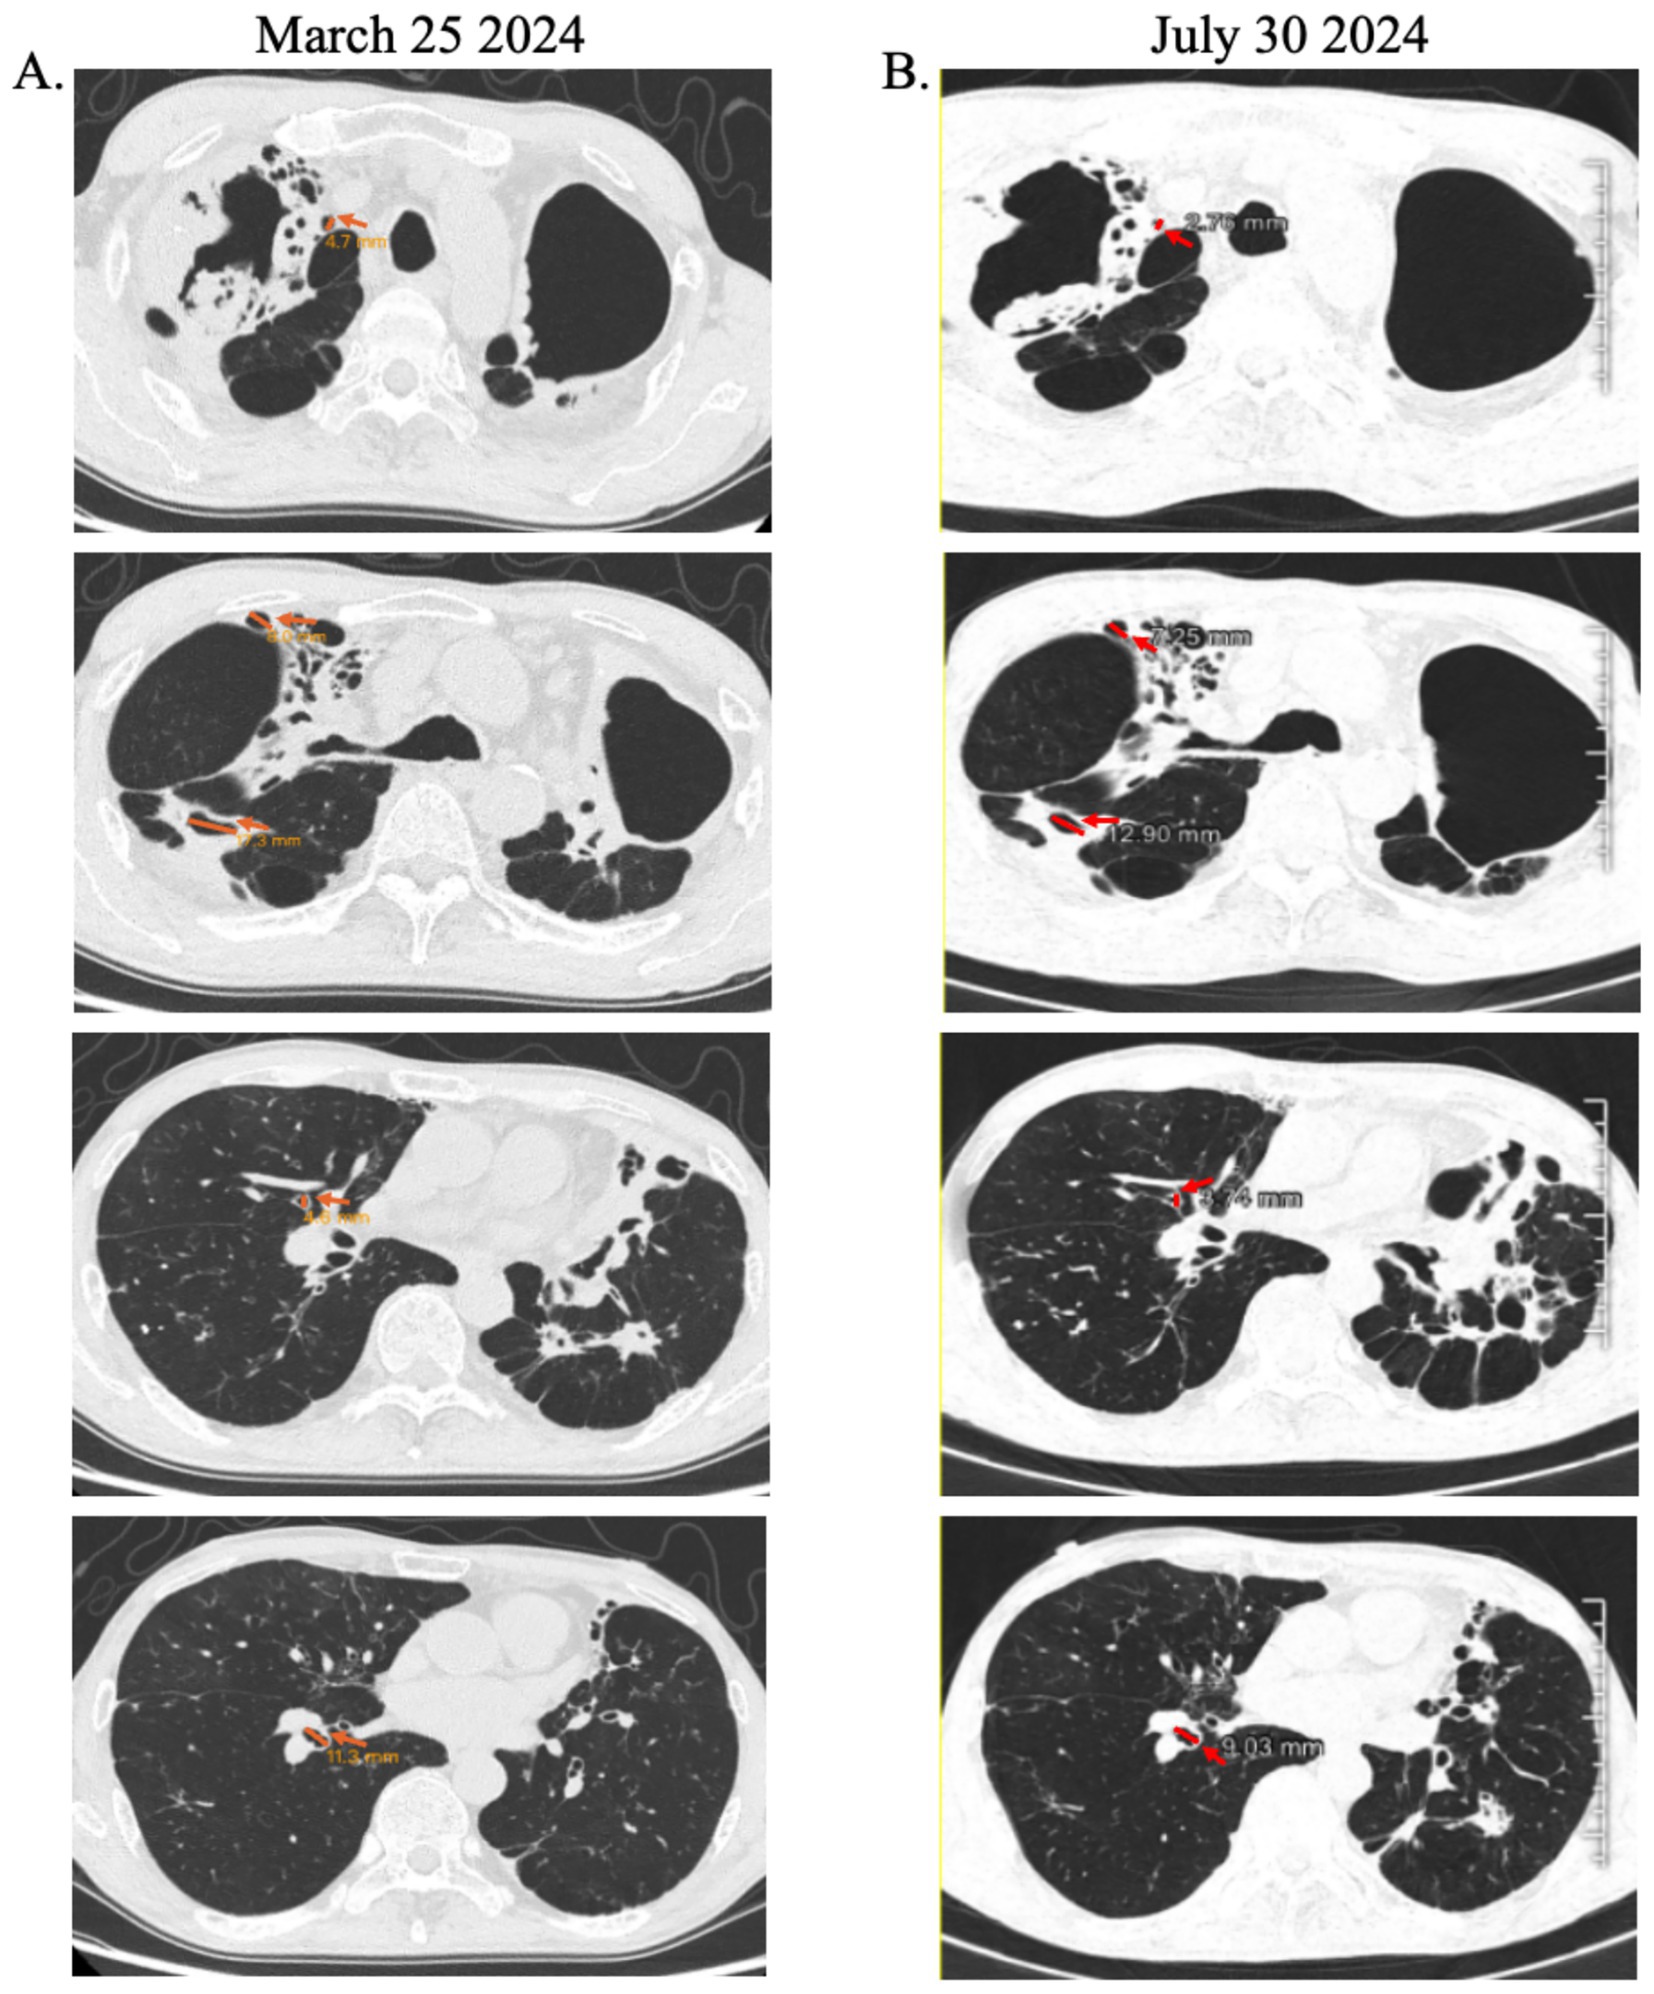

Following three courses of HucMSC-Exos nebulization, the patient was successfully weaned off supplemental oxygen. By August 1, 2024, he exhibited marked clinical improvement in cough, sputum production, dyspnea, activity tolerance (3–5 miles daily), and appetite (BMI: 15.22). His SpO₂ stabilized at 97% on room air. Chest CT revealed partial reduction in cavity size compared to baseline (Figure 1). Post-treatment hematologic analysis showed decreased WBC, neutrophil, monocyte counts, and C-reactive protein, while renal function remained normal, supporting the safety of exosome inhalation (Table 1). Given sustained clinical stability, exosome therapy was discontinued with planned follow-up.

Figure 1

Radiographic evidence of air cavity reduction following HucMSC-Exos inhalation therapy. (A) Baseline chest CT scan demonstrating extensive cavitary lesions (yellow arrows), (B) follow-up scan showing significant reduction in cavity dimensions (red arrows).